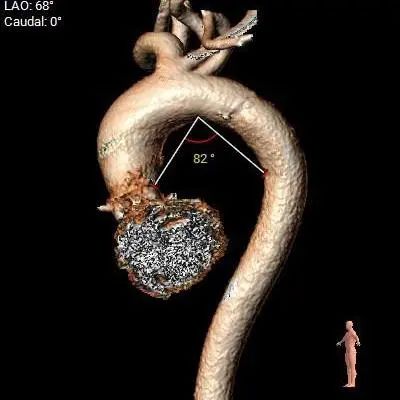

病理特点及手术难点

三叶式主动脉瓣,瓣叶轻中度钙化并明显增厚,人工瓣膜锚定力尚可,左室流出道呈敞口型,综合多平面分析,预估瓣膜释放后有向下位移风险及瓣周漏可能。

左右冠开口高度稍低,综合瓦氏窦及窦管交界内径综合判断,预估左右侧冠脉阻挡风险适中,术中可根据球扩结果进一步判断,必要时行冠脉保护。

非横位心,主动脉弓角度及弓距可,预估术中输送器过弓、跨瓣顺利。

直径20mm TaurusAtlas球囊进行预扩,同时预装TaurusElite AV23瓣膜。瓣环下0-2mm开始定位释放。释放过程中多角度造影,超声辅助定位确定瓣膜最终位置。释放后再次造影确定佐证。